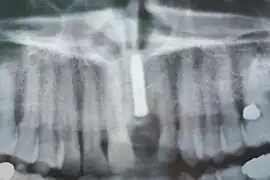

Implants en place. Notez qu'il y a moins d'implants que de dents sur la prothèse.

Radiographie des six implants